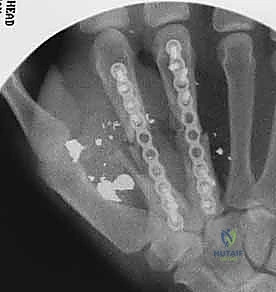

خطوات التثبيت الجراحي - توثيق بصري (Intraoperative Imaging)

يحرص الدكتور هطيف على توثيق خطوات العمل الجراحي لضمان أعلى مستويات الدقة. نستعرض هنا مجموعة من الصور من داخل غرفة العمليات توضح مدى تعقيد ودقة هذه الجراحات:

تتطلب الجراحة انتباهاً خاصاً للأوتار الباسطة والقابضة والأعصاب الدقيقة المحيطة بالعظام. استخدام تقنيات الجراحة الميكروسكوبية (Microsurgery) يضمن عدم الإضرار بهذه الأنسجة الحساسة.